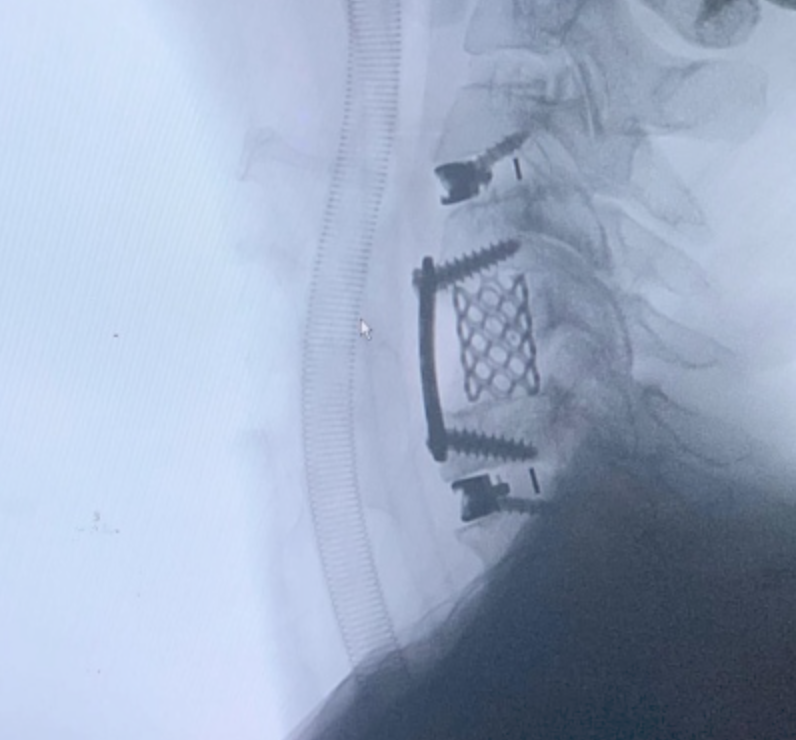

SURGERIES

RESULTS